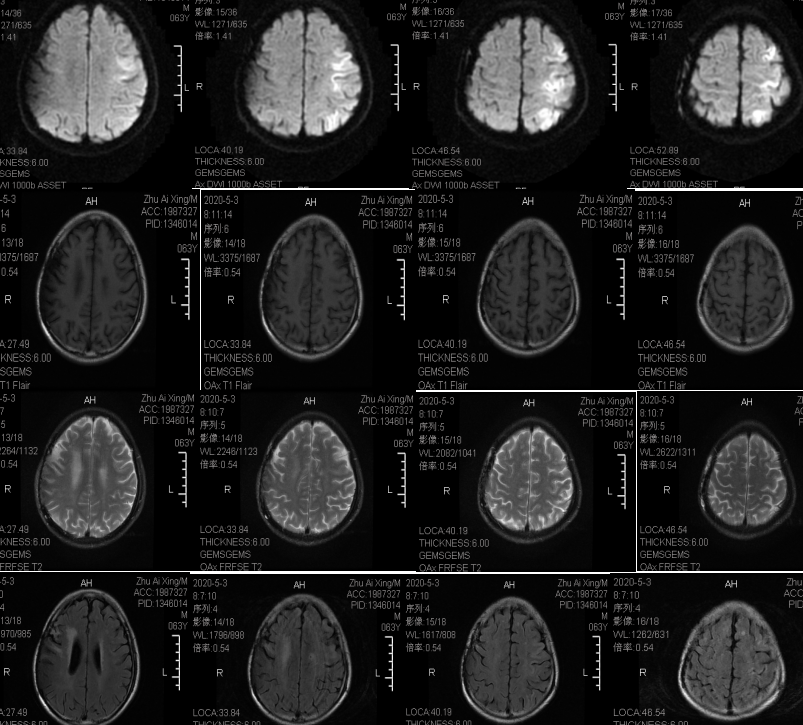

11~脑白质病的mri信号分析与诊断思路

脑白质区内mri斑点状异常信号解读

正确解读磁共振脑白质区内斑点影

影像基础脑白质病变fazekas分级

磁共振报告上别再写缺血灶了请用脑白质高信号fazekas分级